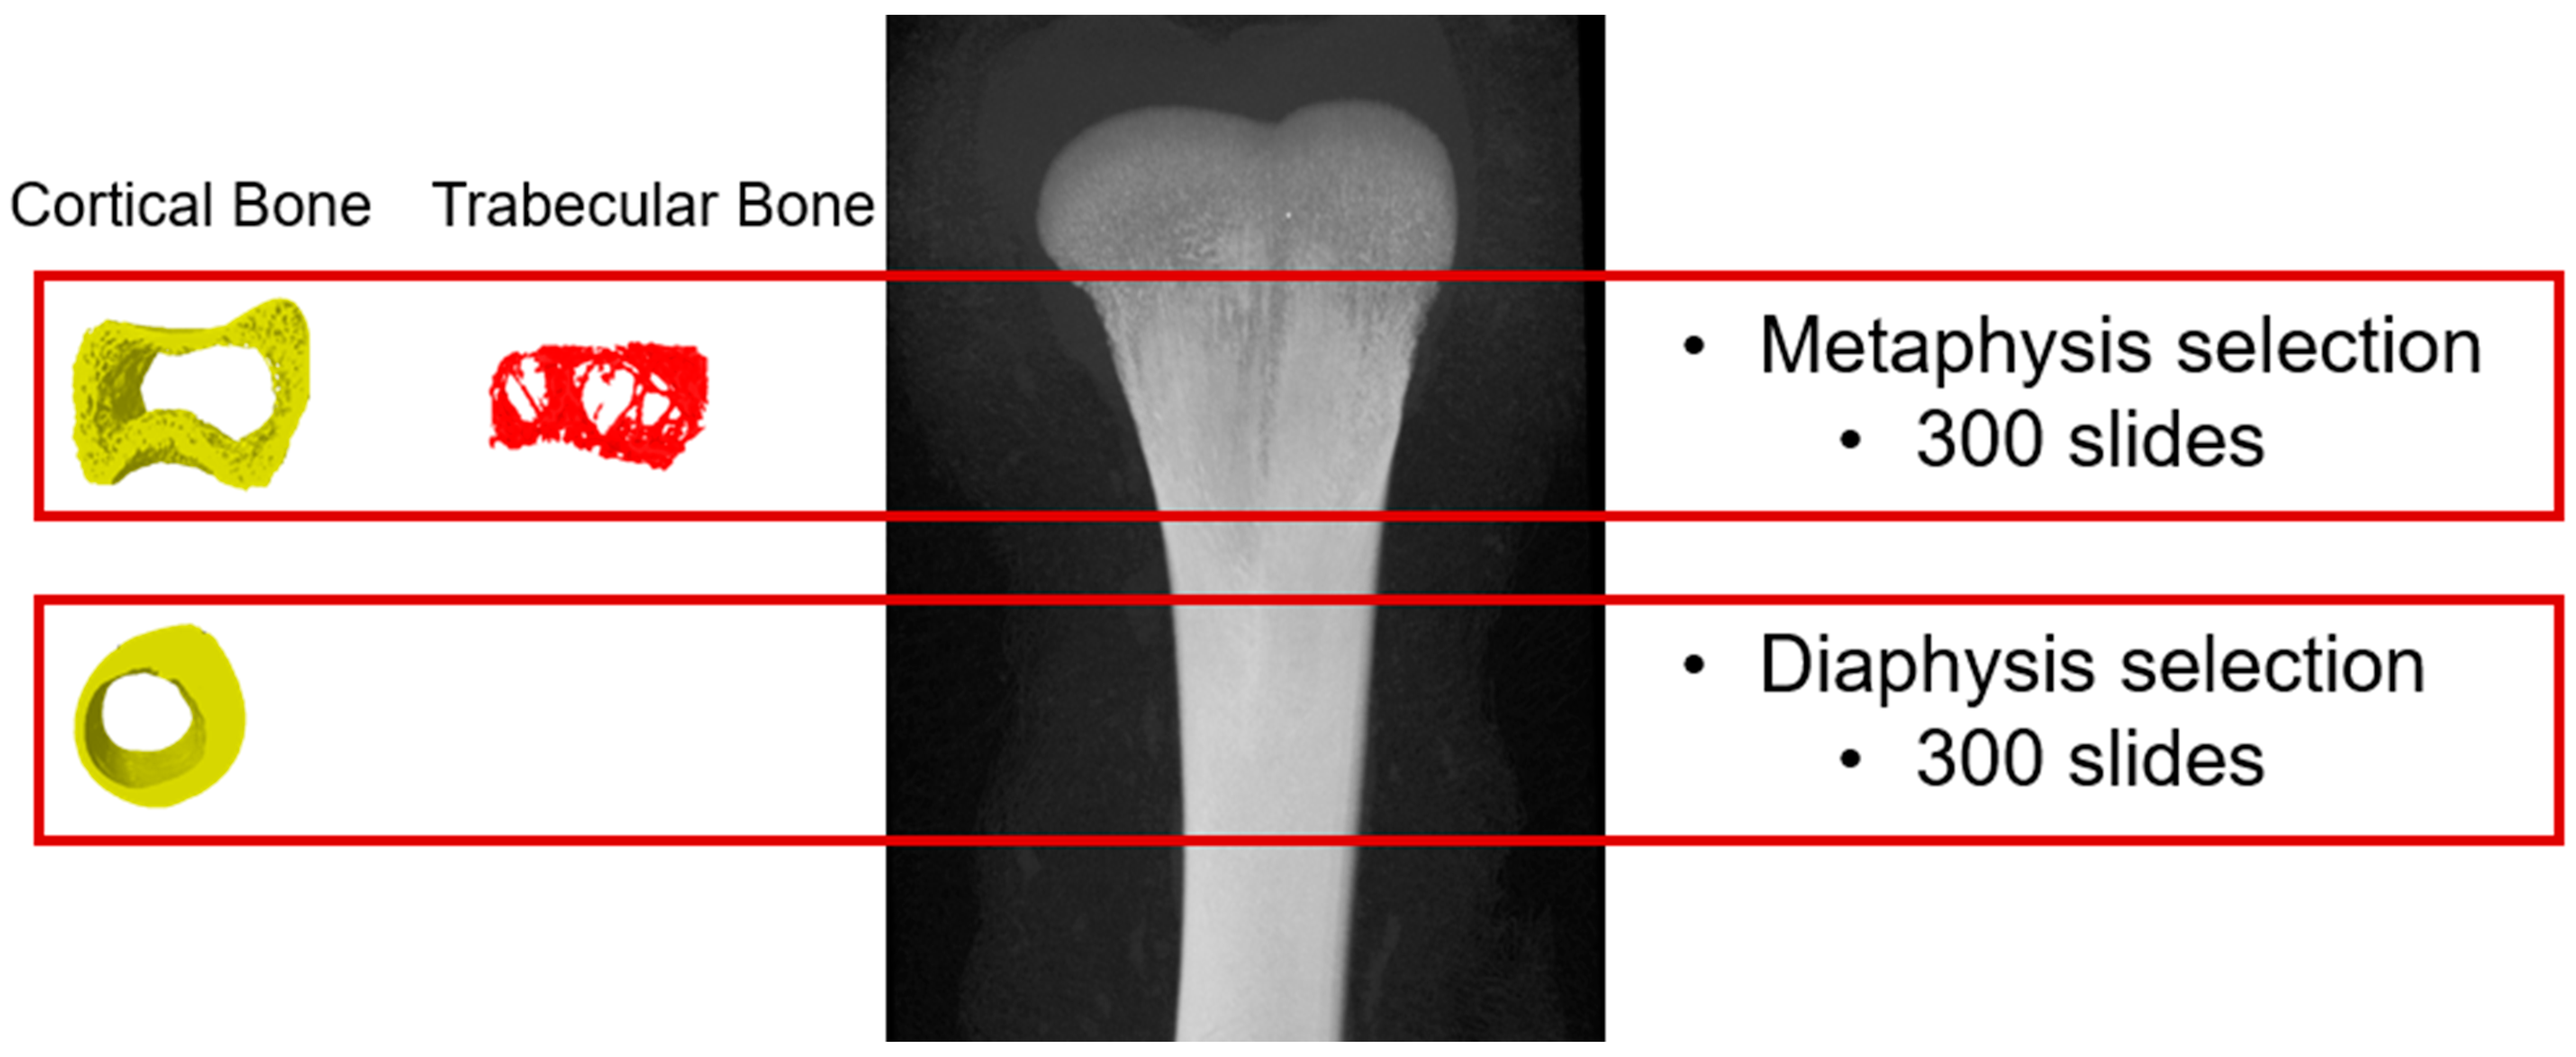

2.3. Microtomography Scanning for Microstructural Analysis of the Femur Bone

3.2.1. Metaphysis Cortical Bone

3.2.2. Metaphysis Trabecular Bone

3.2.3. Diaphysis Cortical Bone